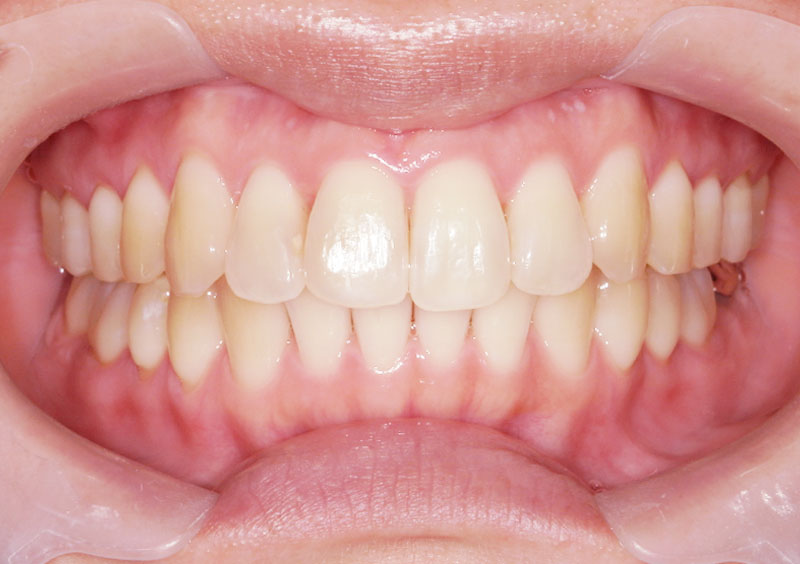

症例03

治療前

治療中

治療後

主訴 | 上の前歯の隙間、噛み合わせが悪い。 |

治療期間 | 2年間 |

治療費 | ¥65,000(税込) |

治療内容 | 上顎に床矯正装置を1装置使用。 |

治療のリスク | 口唇閉鎖力が弱く、 装置だけでは改善が困難。 ワイヤーの調整量を過剰にすると 歯に痛みを感じてしまうため、 調整を繰り返す必要がある。 |